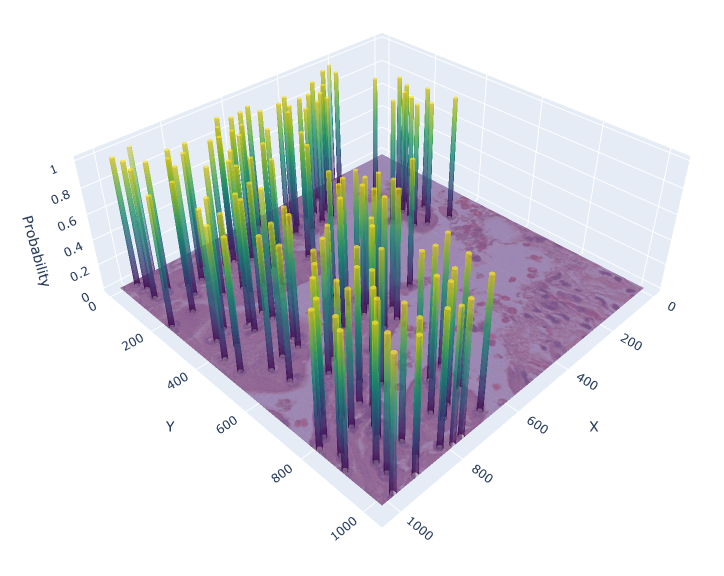

For the circle and soft IS ground truth formats we extract cell detection candidates from the segmentation prediction by applying skimage.feature.peak_local_max on the blurred foreground prediction (Figure 3), where:

Appendix 0.C Ablation study: Different values for soft IS ground truth

The value for soft IS was originally chosen based on a visual review. To investigate, whether there would be a more suitable value, we conducted an ablation study with , analyzing the performance of the soft IS model. Figure 7 shows an example of the soft IS mask for all considered values. The internal train and validation set were used for training and evaluation. The highest mean F1-Score is achieved for , while our initial choice shows a slightly lower performance by -0.6%. Notably, the choice of appears to be a compromise between precision and recall (Table 5). While lower lead to a more precise cell detection, this comes at the cost of a higher number of missed cells (false negatives). The opposite is the case for larger values. Overall, while the difference in F1-Score for and is minor, utilizing for future work is recommended.